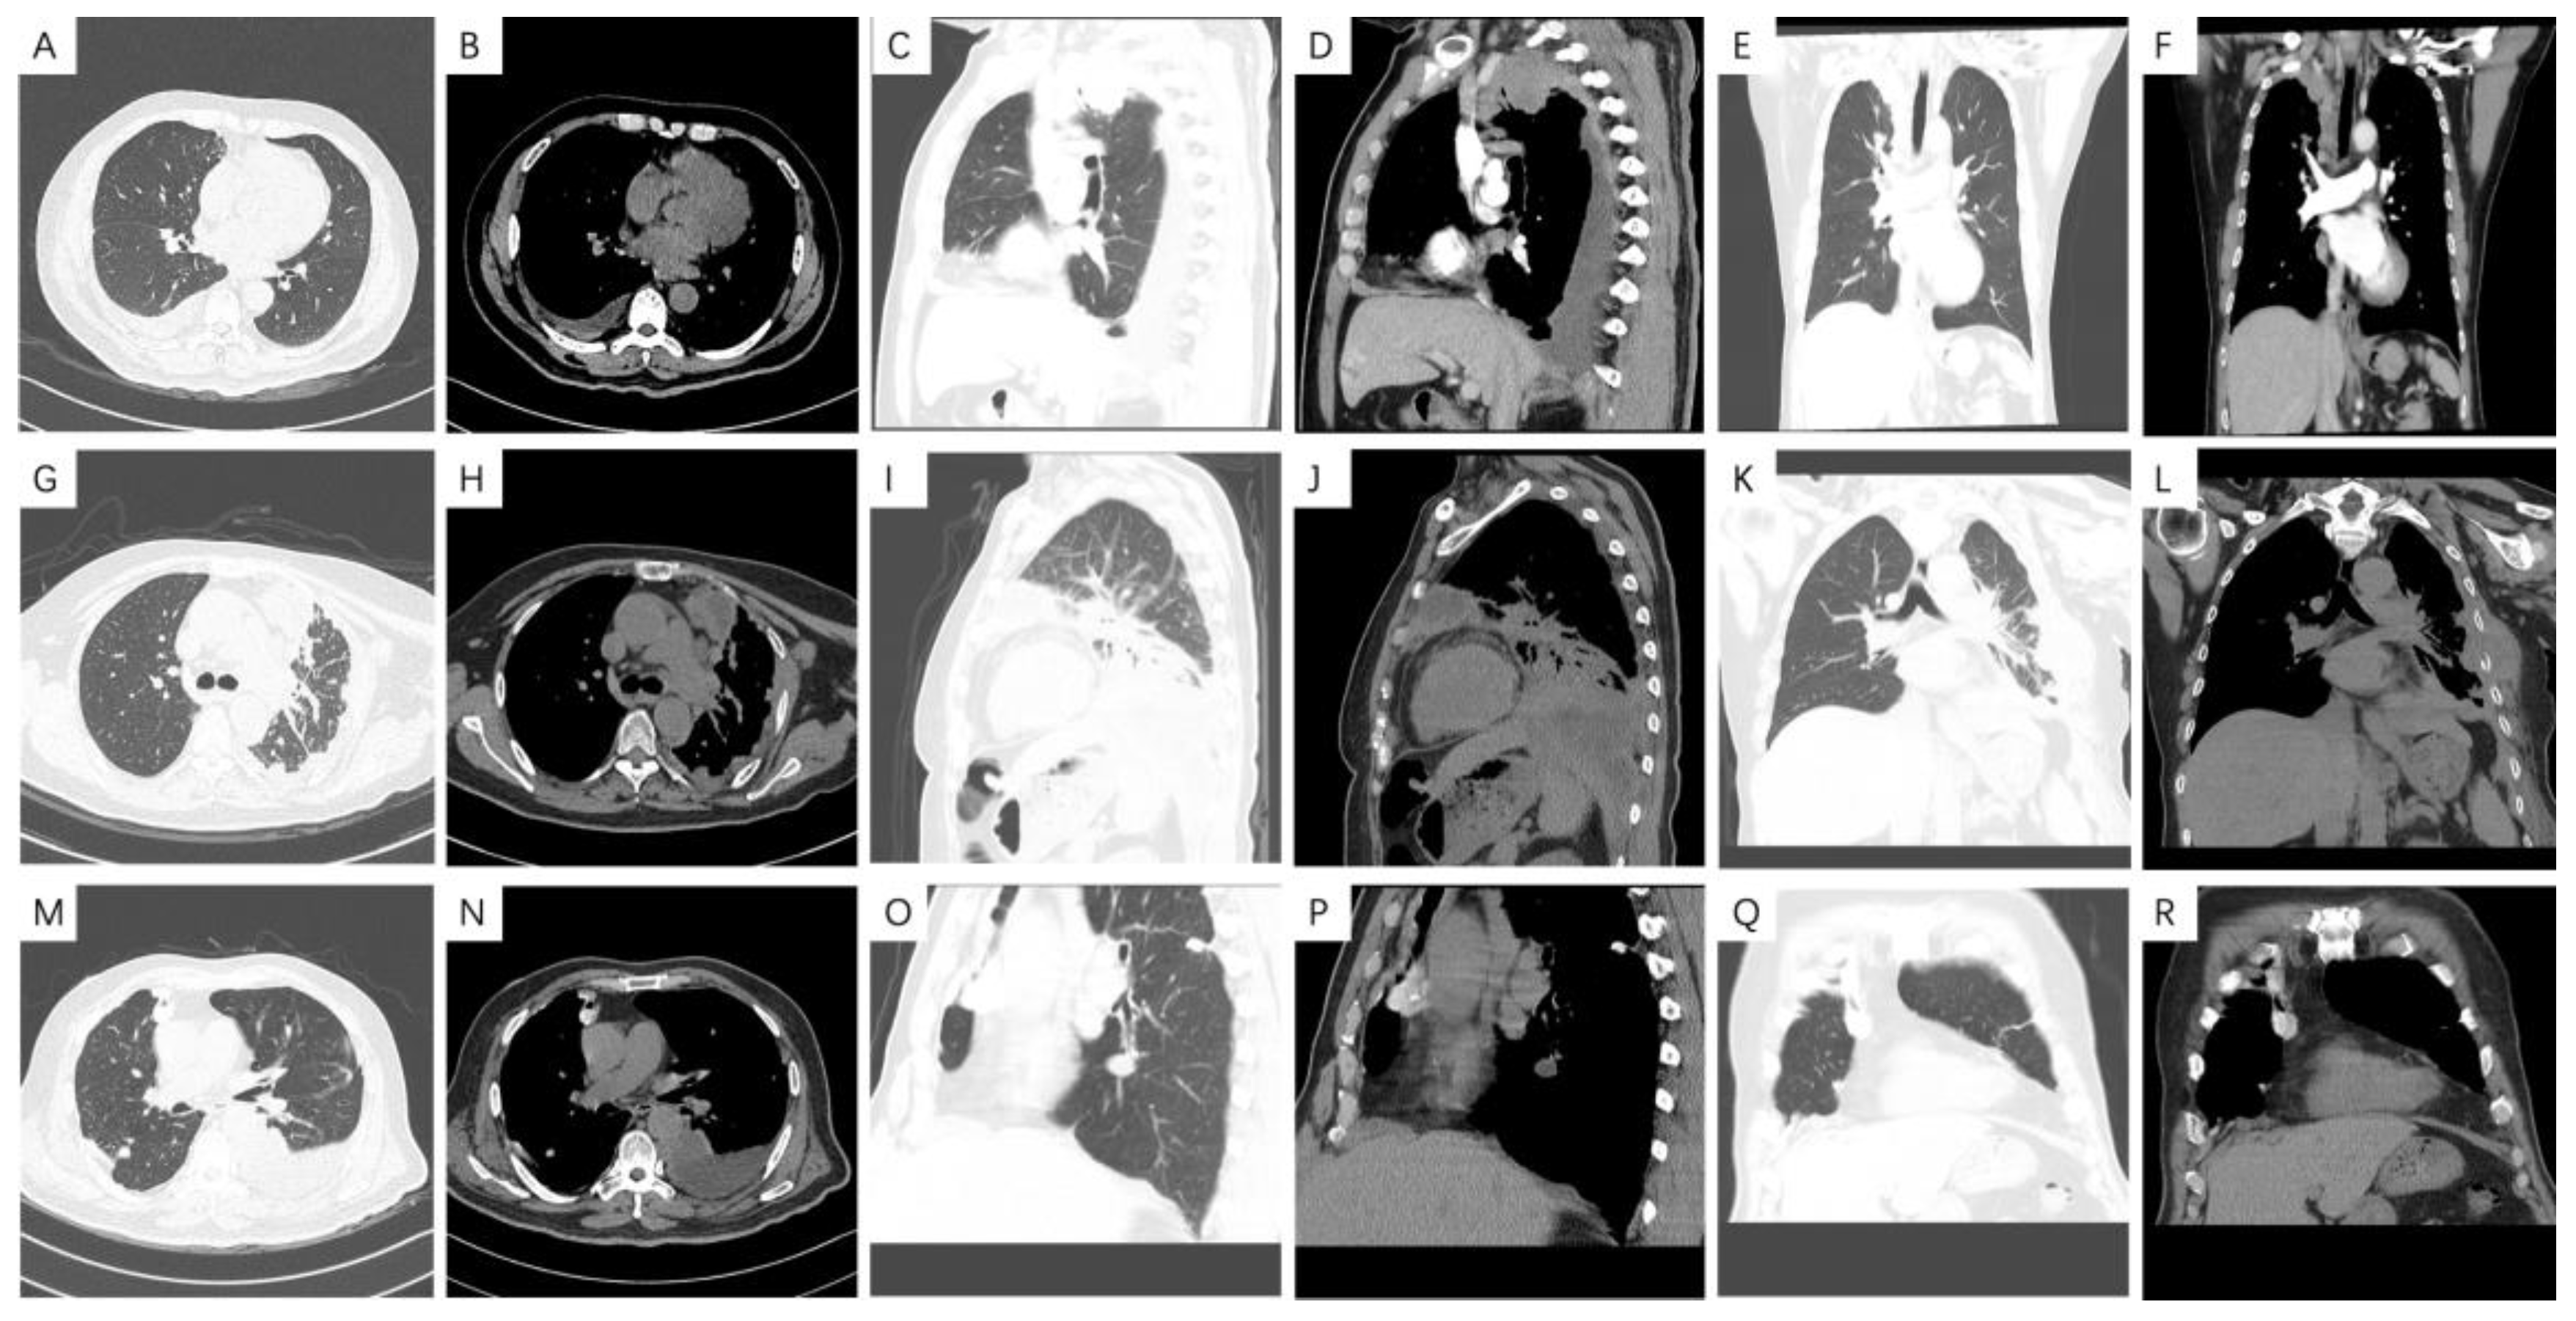

3.4. Radiological Features

4.3. Radiological Characteristics of Malignant Pleural Mesothelioma